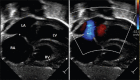

A patent foramen ovale (PFO) is a frequent incidental finding during echocardiography in otherwise healthy children. In most healthy children with a diagnosis of isolated incidental PFO, no further follow-up or intervention is necessary. In some children, PFO is associated with certain clinical syndromes such as cryptogenic stroke, decompression sickness, migraine, and platypnea-orthodeoxia syndrome. This review discusses PFO anatomy, diagnostic imaging, PFO-associated clinical situations, management options, and the role of PFO in certain congenital heart disease. This review also highlights the current deficiency of pediatric data guiding management of these uncommon but important PFO-associated conditions. Future multicenter randomized controlled studies are necessary to guide the management of these unique and challenging PFO-associated conditions.